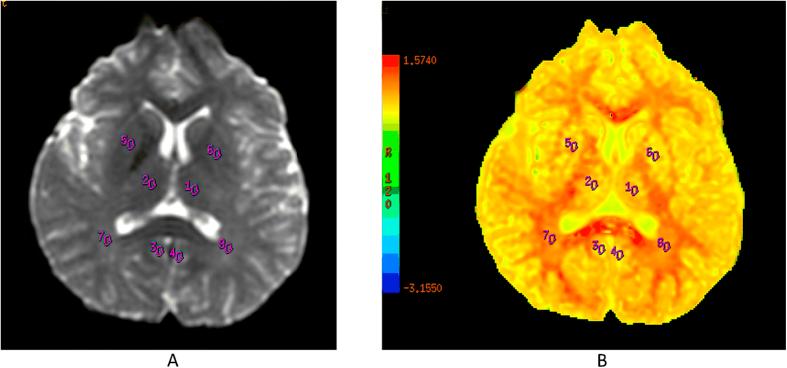

The diagnosis and pathology of neuropsychiatric systemic lupus erythematosus (NPSLE) remains challenging. Herein, we used multimodal imaging to assess anatomical and functional changes in brains of SLE patients instead of a single MRI approach generally used in previous studies. Twenty-two NPSLE patients, 21 non-NPSLE patients and 20 healthy controls (HCs) underwent 3.0 T MRI with multivoxel magnetic resonance spectroscopy, T1-weighted volumetric images for voxel based morphometry (VBM) and diffusional kurtosis imaging (DKI) scans. While there were findings in other basal ganglia regions, the most consistent findings were observed in the posterior cingulate gyrus (PCG). The reduction of multiple metabolite concentration was observed in the PCG in the two patient groups, and the NPSLE patients were more prominent. The two patient groups displayed lower diffusional kurtosis (MK) values in the bilateral PCG compared with HCs (p < 0.01) as assessed by DKI. Grey matter reduction in the PCG was observed in the NPSLE group using VBM. Positive correlations among cognitive function scores and imaging metrics in bilateral PCG were detected. Multimodal imaging is useful for evaluating SLE subjects and potentially determining disease pathology. Impairments of cognitive function in SLE patients may be interpreted by metabolic and microstructural changes in the PCG.

神经精神性系统性红斑狼疮(NPSLE)的诊断和病理学仍然具有挑战性。在此,我们使用多模态成像来评估系统性红斑狼疮(SLE)患者大脑的解剖和功能变化,而不是像以往研究中通常采用的单一磁共振成像(MRI)方法。22例NPSLE患者、21例非NPSLE患者和20例健康对照者(HCs)接受了3.0 T的MRI检查,包括多体素磁共振波谱、用于基于体素的形态学测量(VBM)的T1加权容积图像以及扩散峰度成像(DKI)扫描。虽然在其他基底神经节区域也有发现,但最一致的发现出现在后扣带回(PCG)。在两个患者组的PCG中均观察到多种代谢物浓度降低,且NPSLE患者更为明显。通过DKI评估,两个患者组双侧PCG的扩散峰度(MK)值均低于HCs(p < 0.01)。使用VBM在NPSLE组中观察到PCG灰质减少。检测到双侧PCG的认知功能评分与成像指标之间存在正相关。多模态成像有助于评估SLE受试者并可能确定疾病病理学。SLE患者认知功能的损害可能由PCG中的代谢和微观结构变化来解释。